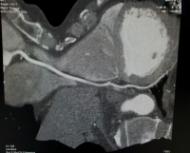

¿QUÉESUNATOMOGRAFÍADECORONARIAS?

Latomografíadecoronariasesunestudio cardiaconoinvasivoqueutilizarayosXpara tomarimágenesdelcorazónyvalorarlaanato‐míadelasarteriascoronarias.

ConlaAngiotacCoronariasepuedentomar imágenesdelcorazónquelate,mostrarcalcio ybloqueosenlasarteriasdelcorazón.

Latomografíacardiacapermitevalorar tambiénlafuerzaconlaquesecontraeelco‐

razón;delamismamaneraqueseevalúacon unecocardiograma.

Enestemismoestudiosepuederealizaruna valoracióncompletadelaaortaparadeterminar siexistenaneurismasodiseccionesdelaaorta.

Cuandosedetectalesióndeltroncodelacoro‐nariaizquierdaocuandohaylesiónde3arterias coronarias;sedebederealizarunacirugíadeby‐passconimplantesdearteriamamariainterna.

Sintintedecontraste,sepuedeusarpara medirlacantidaddecalcioenlasarteriasdel corazón.Supuntajedecalciolesdaalosmé‐dicosunaideadecuántaplacahayenlas arteriasdelcorazónqueaúnnohacausado problemas.Supuntajedecalciopuedeayudar apredecirsuriesgodeataquecardíaco.